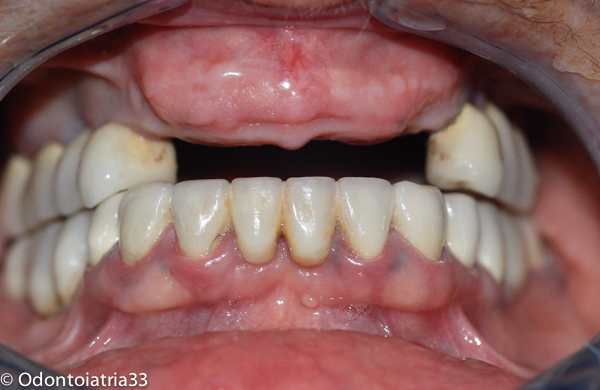

Il caso clinico che segue tratta di paziente donna di 67 anni, collaborante, con anamnesi positiva solo per ipertensione arteriosa (in terapia e ben compensata), con un discreto controllo dell'igiene orale, non fumatrice. La paziente è giunta alla nostra osservazione, nonostante un'estetica ancora accettabile, con mobilità del vecchio lavoro protesico,con problematiche parodontali a carico degli elementi portanti il ponte e con frattura radicolare dell'elemento 12.

Si è deciso pertanto di procedere all'estrazione degli elementi dentari 13-12-11-21-23 riabilitando per due mesi la paziente con un provvisorio mobile in acetato. Contrariamente a quanto succede normalmente dove la problematica maggiore con cui fare i conti è il quantitativo osseo ridotto e di conseguenza l'aumentata distanza interarcata, in questo caso ci siamo trovati a dover affrontare un ridotto spazio interarcata con rapporti intermascellari sfavorevoli in senso antero-posteriore oltre che cranio-caudale.

I primi provvisori avvitati sono stati posizionati dopo 6 settimane dall'intervento chirurgico di inserimento implantare e rimodellamento. I provvisori avevano ancora per ragioni tecniche un rapporto di overjet da correggere poi con i definitivi.

Dopo 5 mesi di provvisori avvitati man a mano modificati la paziente è stata protesizzata con definitivi in zirconio e ceramica stratificata.